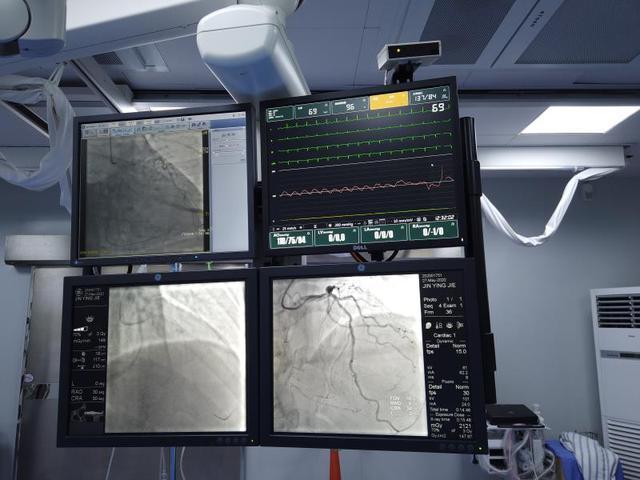

沈阳市第六人民医院为满足患者们日益迫切的刚性医疗需求,在医院“大综合 强专科”强势转型发展下,引进心血管内二科陈用贵主任及其团队,日前成功为急性冠脉综合征的患者,独立实施了冠状动脉介入手术。

入院后于2020年5月27日,为其经桡动脉路径,行冠状动脉介入手术。患者锁骨下动脉极度迂曲,冠脉开口异常,手术难度很大。在陈用贵主任团队和该院导管室紧密合作下,成功置入支架,解除主要狭窄病变,术后患者心绞痛症状缓解,各项指标基本正常,患者目前恢复状况良好。